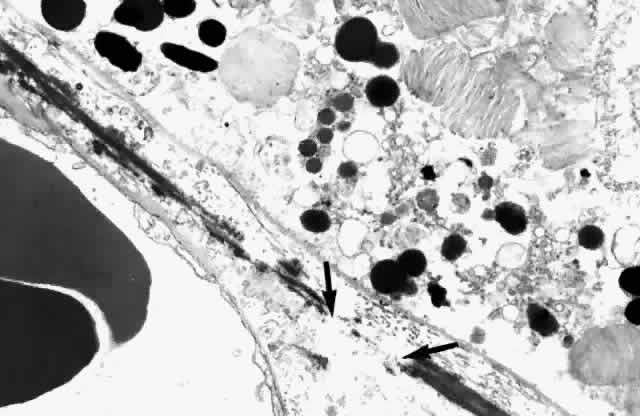

The nuclei of the smooth muscle cells are cigar shaped and often contain one or two nucleoli. The cytoplasm contains mitochondria, smooth and rough endoplasmic reticulum, pinocytotic vesicles along the surface of the membrane, and many myofilaments (Fig. 20). The filaments are long and parallel to each other. Dense, osmiophilic thickenings on the myofilaments may represent Z bands where the filaments fix for contraction.17 As the arteries diminish in caliber, they become arterioles, which have only an intermittent layer of smooth muscle cells and no internal elastic lamina. The adventitia is continuous with collagen fibers in the intervascular spaces. The endothelium is continuous, and the cells are covered by basement membrane. There is more collagen around the precapillary arterioles than around the postcapillary venules.

Fig. 20. Pinocytic vesicles (small arrows) and myofilaments in smooth muscle cell (open arrow). (× 43,500)